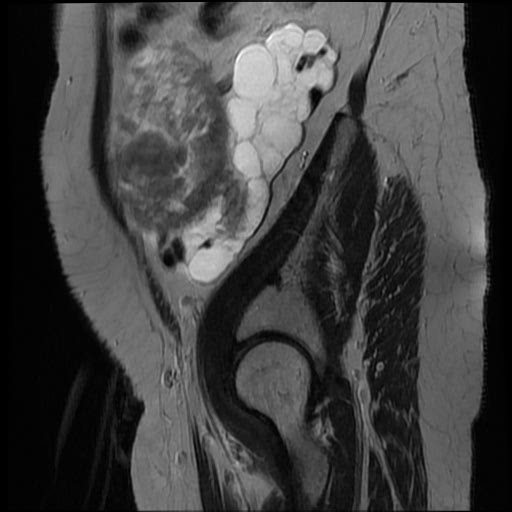

КТ ретроперитонеального фиброза: Изображения и диагностика